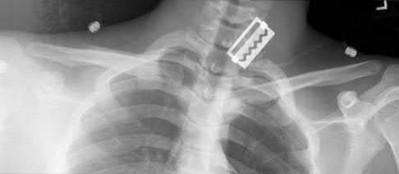

1. # A 32-year-old male sustains the injury shown in Figure A and undergoes treatment as shown in Figure B. Following placement of this implant, what is the best technique to confirm it is not too proud proximally?

The safe zone for tibial nail placement as seen on radiographs is just medial to the lateral tibial spine on the anteroposterior radiograph and immediately adjacent and anterior to the articular surface as visualized on the lateral radiograph.

Tornetta et al specifically located the safe zone for nail entry in a study using fresh frozen cadaver knees. The authors found that the safe zone for nail placement is located 9.1+/-5 millimeters lateral to the midline of the plateau and three millimeters lateral to the center of the tibial tubercle. The width of the safe zone averaged 22.9 millimeters and was as narrow as 12.6 millimeters.

The starting point of the of the nail can be best viewed on the lateral knee radiograph, an example of which is shown in Illustration A. Illustration B shows the "sweet spot" for nail insertion as defined by Tornetta.